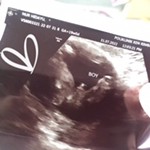

Hai semua, nak tanya. Boleh percaya ke kalau scan jantina week 18? Ke masih samar2 sebab kecik lagi?

Hi sis, saya haritu pun scan 18w, nampak samar samar jugak. Kalau ada rezeki lebih, sis boleh buat details scan pulak. Macam saya, nanti 23w nak buat details scan untuk tengok betul betul keadaan baby and gender ☺️

nk scan boleh je 18week, dh boleh nmpk, sebaiknya 20 week keatas.. kalau boleh percaya atau tidak tu bgi sy cukup dijadikan rujukan la sbb ada yg scan lain, keluar lain..

Masa 19w dah scan kat kk, nampak mcm girl. Tapi belum beli apa2 lagi barang baby. Sbb nak tggu detail scan masa 21w, sekali tgk gender..scan dengan pakar o&g..

sy dh scan 19w.. doc ckp mmg sahih dan pasti boboyy 😅